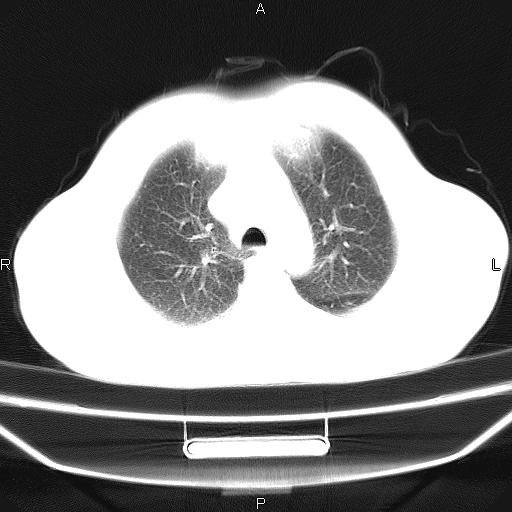

患者,男,40岁。间断发热,咳嗽二十余日。体温最高达38.9° 在当地诊所抗炎治疗三天后体温降至正常,患者自行停药。今又发热。胸片示,左下肺阴影。

左下肺片状高密度影,境界模糊,密度不均,考虑感染性病变可能性大,建议抗炎治疗后复查。左肺门增大,不除外占位性病变,必要时支气管镜检。